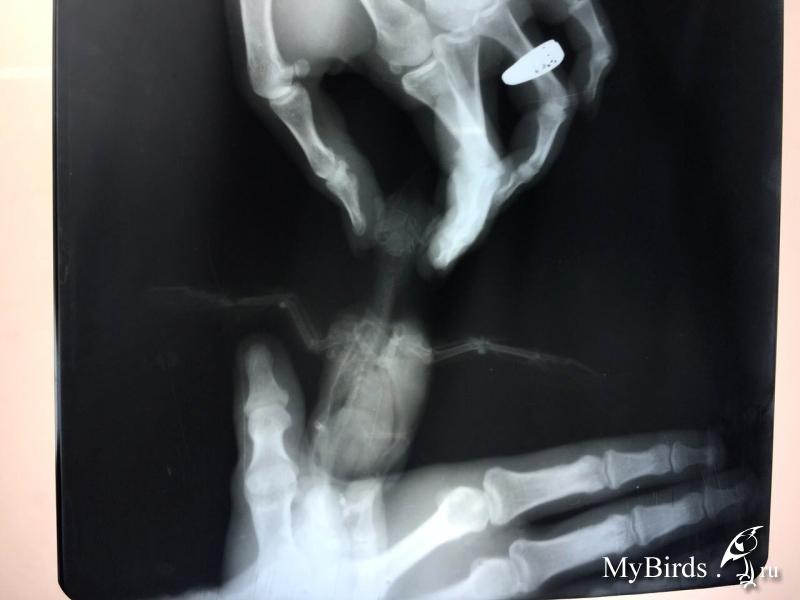

Добрый день! Подобрали стрижа с переломом. Подскажите в отношении лечения что можно сделать.

значительного смещения нет, шанс есть. но не 100%.

при таком переломе рентген в полной раскладке опасен( можно доломать, были случаи.

понятно... тогда половину написанного выше можно забыть. просто перед рентгеном крыло удачно сложили. собственно, стрижу с открытым переломом рентген делать особо незачем. разве что убедиться, что нет других повреждений.

птица не полетит. стрижи не летают после переломов со смещением. это пмж.